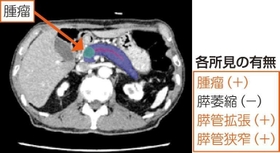

神戸大のチームは早期発見に向けて、がんの所見となるしこり(腫瘤)の発見以外に、膵臓の萎縮、膵管の拡張・狭窄といった前段階で疑われる異常にも着眼した。それらの特徴を含む1千の症例を、富士フイルムに提供してAIに学習させ、専門医でなくても精度が高く、がんが疑われる前段階で発見できる技術開発に成功した。